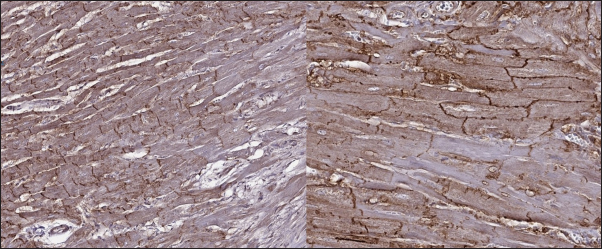

Fig. 6. Immunohistochemistry. HCM group. Left—Transverse section, Cx43 proteins accumulated in the outer membrane periphery of the cardiomyocytes. Stained with Cx43 antibodies. Right—Longitudinal section, Cx43 proteins found in zones of cell-to-cell contact, but reduced in fibrotic and para-fibrotic zones. Stained with Cx43 antibodies.

In the myocardium of cats with HCM we found a typical myocardial fibers disarray, with myocytes presented as thickened stripes branching in chaotic ways. Moreover, significant interstitial fibrosis was observed. Some myocytes were hypertrophied with multiple eccentrically located nuclei. Masson’s trichrome-stained samples showed myocardial fibrosis with interstitial and patchy patterns distributed around arteriolas and deep in the tissues (Fig. 5). Immunohistochemical staining with anti-Cx43 antibodies showed almost intact intercalated disks morphology in unaffected zones, but Cx43 expression began to fade near areas of developed fibrosis. In the transverse axis, we found increased expression of Cx43 on the lateral membrane (Fig. 6). In cardiomyocytes directly connected to the fibrotic tissue, cell-to-cell contacts were pale with almost no staining (Fig. 7).